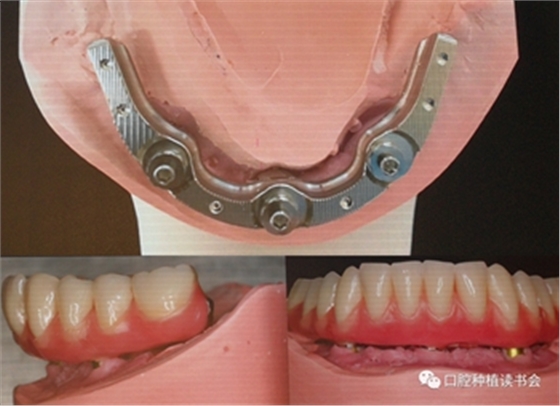

先植入中央種植體后,卸下定位導(dǎo)板,安裝V形導(dǎo)板,完成兩側(cè)種植體植入,試戴支架確認(rèn)種植體角度正確,使用光固化樹(shù)脂固定預(yù)制件,調(diào)整被動(dòng)就位后,轉(zhuǎn)移基臺(tái)轉(zhuǎn)移種植體位置(圖8)。

圖8 在V形導(dǎo)板引導(dǎo)下,完成兩側(cè)種植體植入,轉(zhuǎn)移種植體位置

技師在模型上完成預(yù)成支架+樹(shù)脂義齒的制作,戴入口內(nèi)完成即刻負(fù)重,手術(shù)后兩個(gè)月觀察種植體軟硬組織整合良好(圖9、10)。

圖9 手術(shù)當(dāng)天制作的正式修復(fù)體

圖10 手術(shù)后兩個(gè)月觀察種植體軟硬組織整合良好,修復(fù)體使用良好